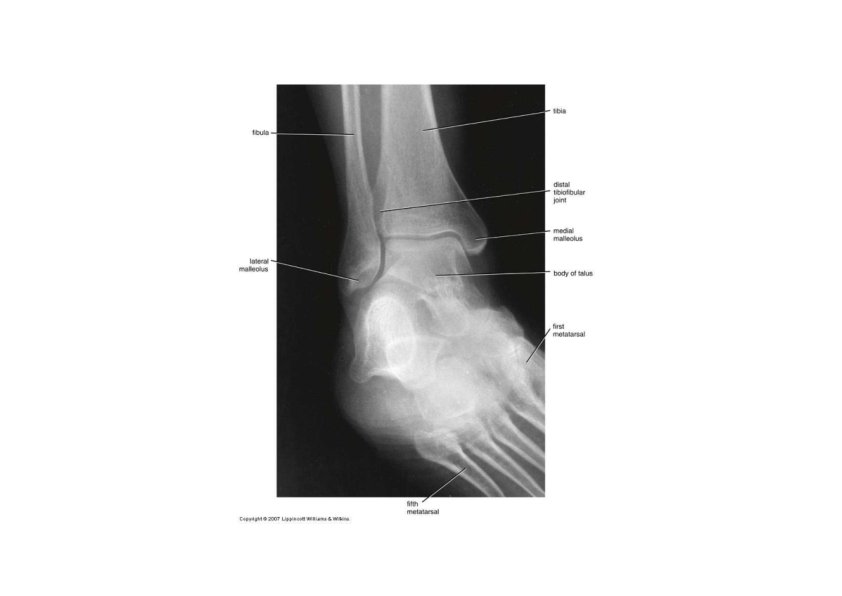

Tibia and Fibula • Tibia • medial & larger bone of leg • weight‐bearing bone • lateral & medial condyles • Intercondylar …… • tibial tuberosity for patellar lig. • proximal tibiofibular joint • medial malleolus at ankle • fibular notch • Fibula • not part of knee joint • muscle attachment only • Head, neck, shaft • lateral malleolus at ankle

Surface Anatomy of Tibia & Fibula • Tibial tuberosity • Anteromedial surface of tibia • Head of fibula • Medial malleolus • Lateral malleolus

Tarsus • Proximal region of foot (contains 7 tarsal bones) • Talus = ankle bone (articulates with tibia & fibula) • Calcaneus ‐ heel bone • Cuboid, navicular & 3 cuneiforms